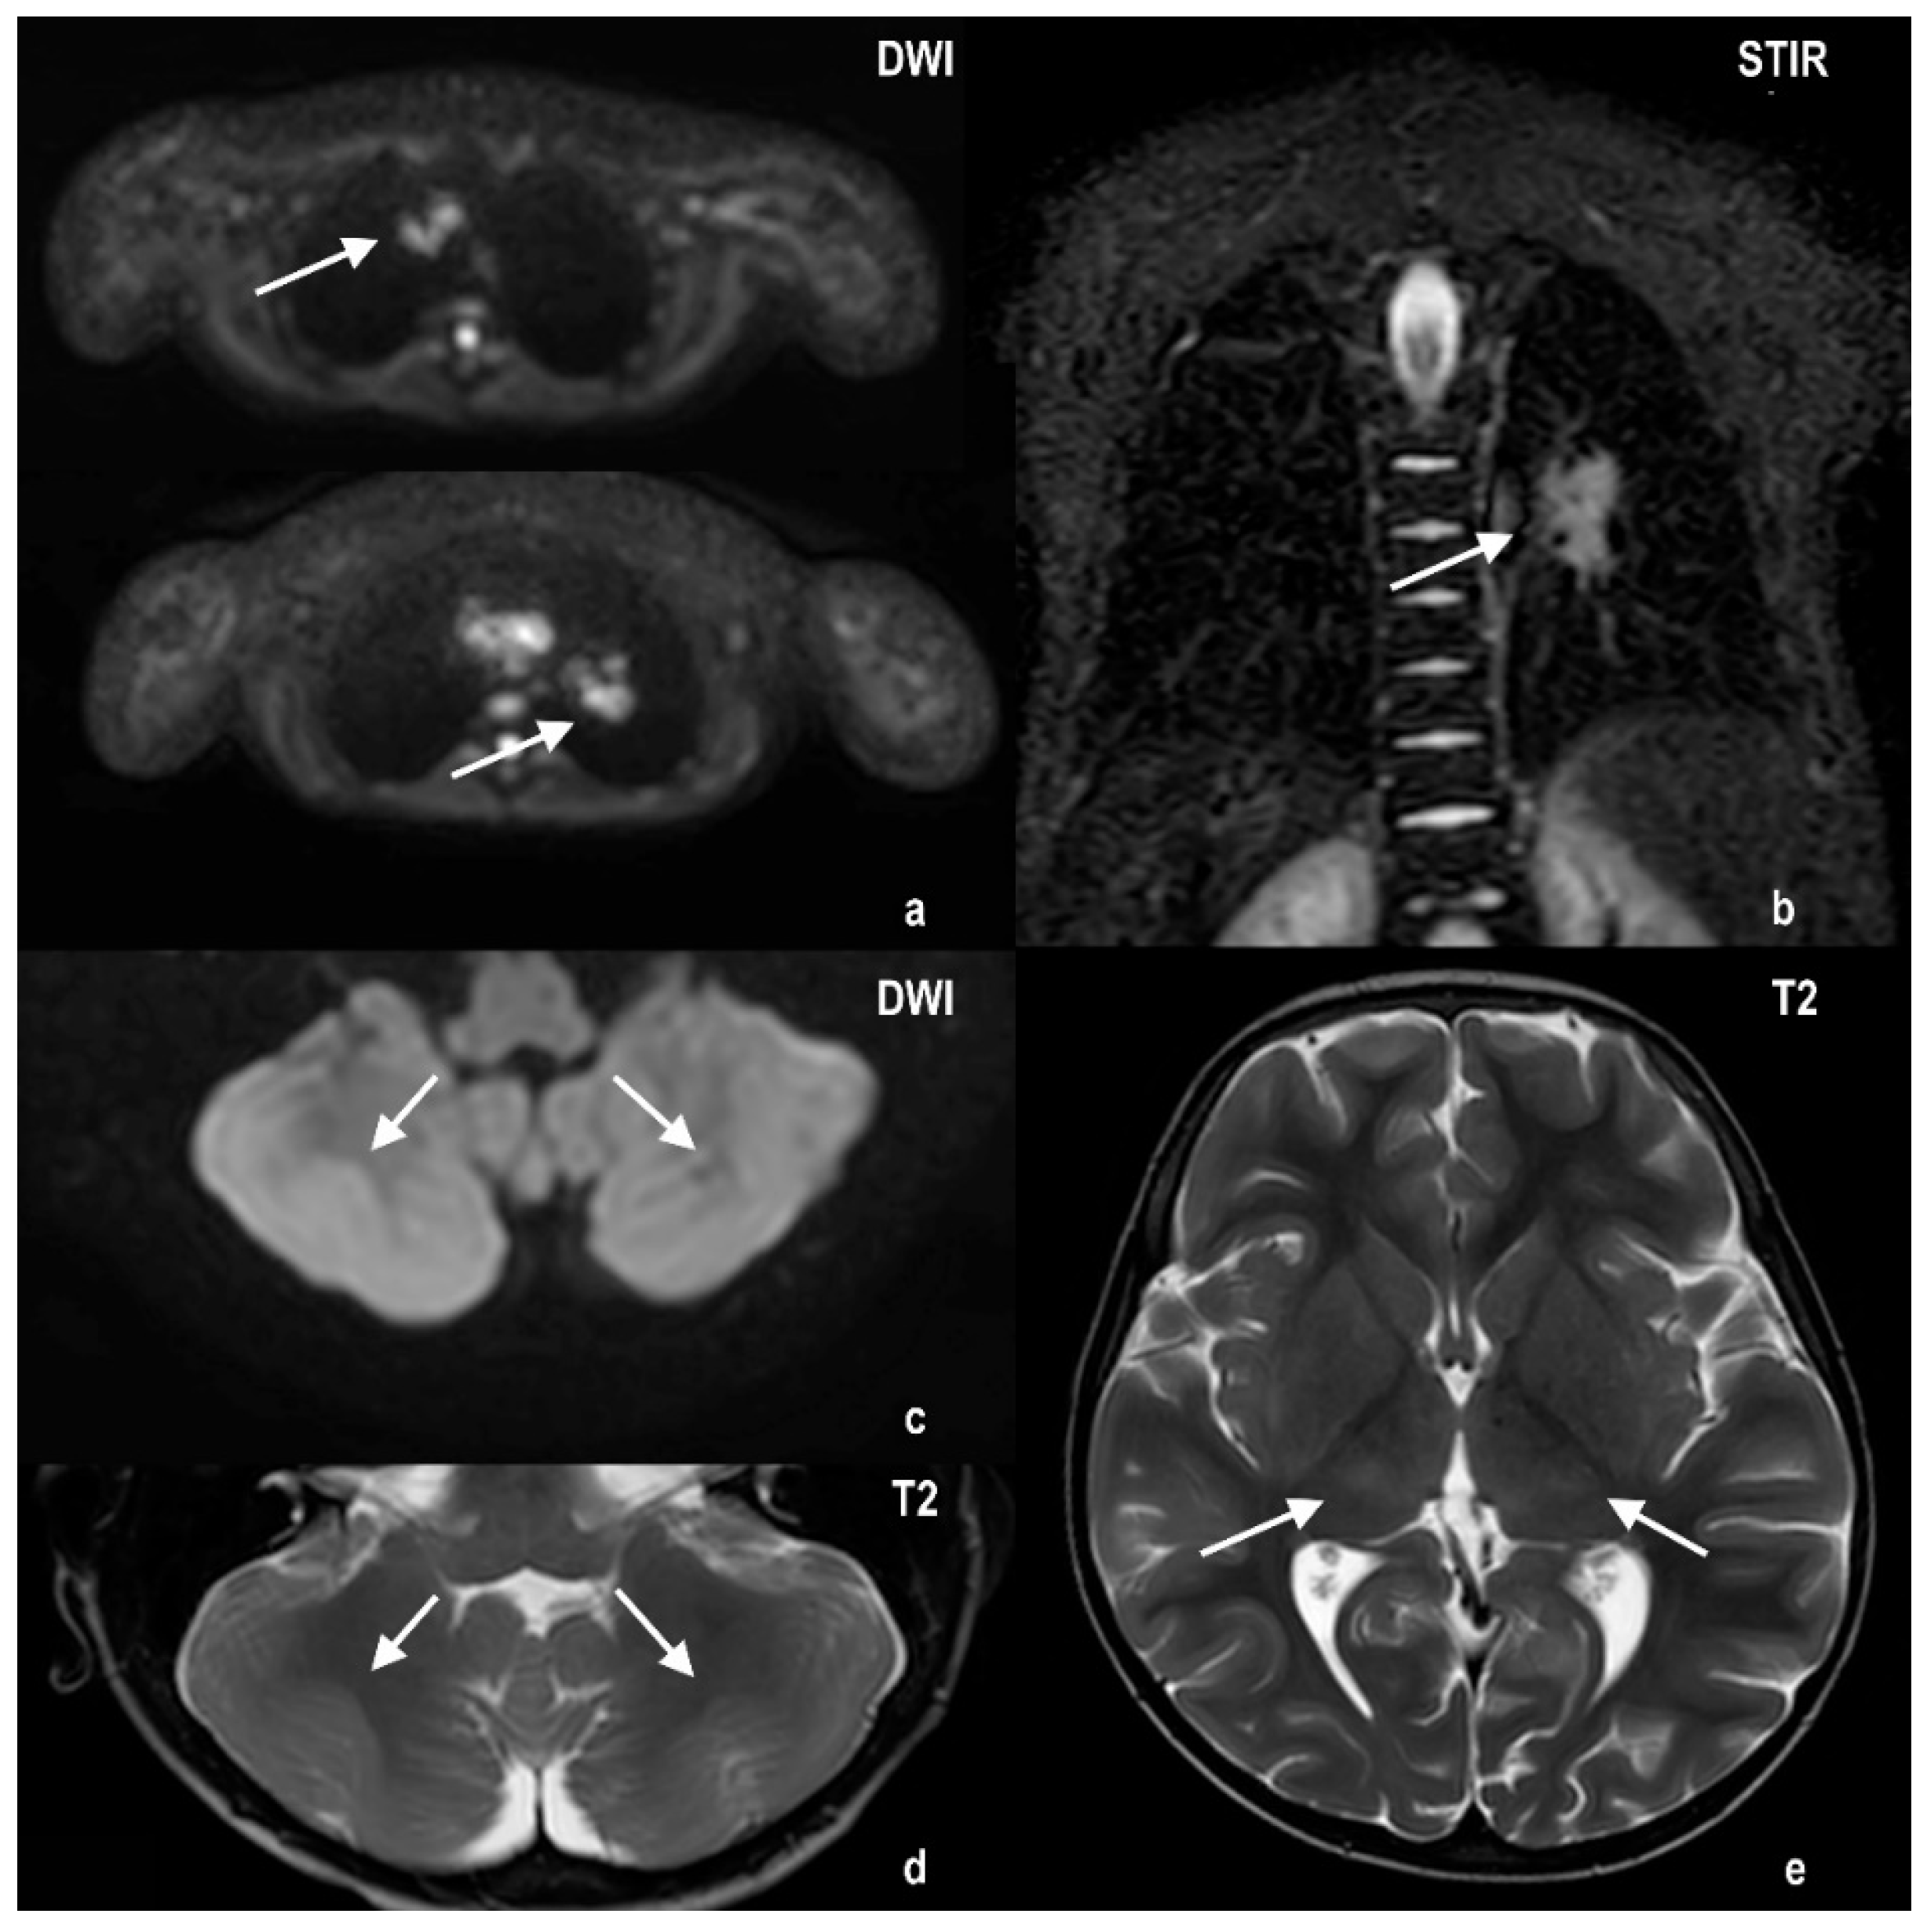

2.1. Case 1

2.2. Case 2